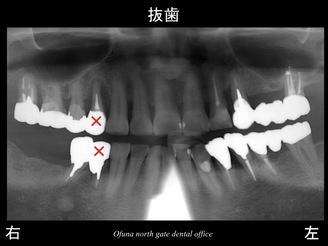

以下が初診時のレントゲンです。

『下顎右側の奥歯が欠損しており、噛めない!』

『上顎右側の奥歯がグラグラしている!』

との問題で来院されました。

右下の奥は2歯分欠損していました。

右上もグラグラです。

また、この症例は 下顎右側の欠損 と 上顎右側のグラグラしている歯 以外にも問題がありました。

下顎の右側の1歯が歯根破折 していたのです。

やはり神経のない歯は脆いです。

そのため、抜歯が必要な部位は以下になります。

それでは、上記の2歯を抜歯した場合の インプラント治療計画は どのようになるのでしょうか?

下顎が3歯欠損、上顎が1歯欠損になりますので、

以下のようなことになります。

本当にこの計画で良いのでしょうか?

他の残っている歯の将来性はどうなのでしょうか?

もし、下顎のインプラント間にある歯がダメになったらどうなるのでしょうか?

下顎のインプラント間にある歯は 神経がない歯です。

この歯がダメになると…

また、インプラントを追加することが必要になってしまいます。

そのため、将来性を考えれば、先程のインプラント間にある歯は抜歯した方が良いのです。

×印と×印を抜歯すると最終的な治療計画は、以下のようになります。

つまり、下顎の右側の奥は2本のインプラントでブリッジとすることが可能になるのです。

こうした方が最終的なインプラントの本数も少なくなります。

最小限のインプラントの本数で将来性の高い治療計画となったのです。